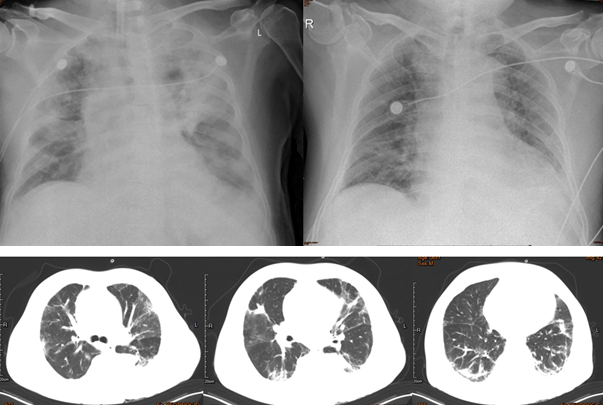

患者,男性,69岁。主诉“发热、气喘、咳嗽、咳痰1个月”。1个月前(2021年3月14日)患者因“发热3天加重伴呼吸困难6小时”于当地医院住院治疗,入院后给予气管插管、抗感染(哌拉西林他唑巴坦+头孢他啶)、化痰、护胃、升压药物、血管活性药物等治疗;3月22日脱机拔管,3月27日患者病情反复,再次出现呼吸衰竭,再次气管插管后由救护车转入我院进一步治疗,给予去甲肾上腺素+多巴胺升压等治疗,为求积极救治转入RICU。胸部X线片提示重症肺炎(左下肺),拔管后复查胸部CT可见肺部病变好转。

图片

送检患者BALF标本行mNGS和ptNGS检测,mNGS回报金黄色葡萄球菌(序列数1759),铜绿假单胞菌(序列数979)。ptNGS也查到了铜绿假单胞菌和金黄色葡萄球菌,另外还检出鲍曼不动杆菌、粪肠球菌及巨细胞病毒。